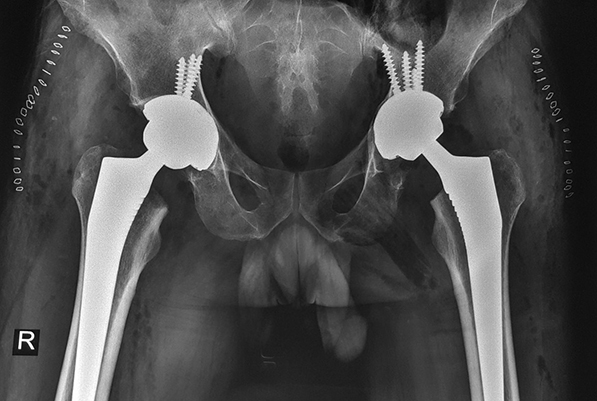

Iz lične foto-dokumentacije doc. dr Barjaktarovića:

Obostrana artroplastika kolena u jednom aktu-stryker |

Bilateralna artroplastika

Ukoliko se operacija kukova ili kolena planira unilateralno, u dve odvojene operacije, pauza između artroplastike levog, odnosno desnog zgloba, treba da je najmanje tri meseca. Ali, kod mlađih, zdravih ljudi sa obostranim oštećenjima zglobova, moguća je i totalna bilateralna artroplastika zglobova u jednom aktu - tokom jedne operacije, endoprotezama se zamenjuju oba kuka ili oba kolena. Poslednji stadijum obostrane koksartroze, ili obostrane gonatroze, kod vitalnih i relativno zdravih ljudi, koji nemaju pridružene bolesti, indikacija su za ovaj složeni zahvat, koji dr Barjaktarović uspešno - bez ikakvih komplikacija - izvodi već više od dve decenije.

Iako su pacijenti kojima se menjaju kolena uglavnom starije životne dobi, i u tim slučajevima se kao kandidati za bilateralnu artroplastiku biraju oboleli od gonatroze koji su dobrog opšteg stanja, sa oštećenim kolenima ali bez drugih bolesti. Kod mladih ljudi je artroplastika kolena retko indikovana operacija, najčešće zbog upalnog reumatizma (reumatoidni artritis i dr), Rajterovog sindroma, ankilozirajućeg spondilitisa i dr.

Sa više od stotinu bilateralnih artroplastika kuka i više stotina artroplastika kolena od kojih su mnoge izvedene u jednom aktu, dr Barjaktarović naglašava da obostrana zamena zgloba, a posebno kolena, zahteva izuzetno iskustvo i znanje, kao i umeće i dobru uvežbanost hirurga i operativnog tima (ortopeda, anesteziologa, instrumentarki i ostalog uključenog osoblja). Svaka artroplastika je invazivna, teška i rizična hirurška intervencija, a kad se u istom aktu operišu oba zgloba, faktori rizika kojima je pacijent izložen dvostruko su veći, dodaje naš sagovornik. Veliki zglobovi kukova u blizini su vitalnih organa, trbuha, grudi, venskih spletova, te je veća mogućnost da dođe do razvoja duboke venske tromboze ili drugih komplikacija. Uvećani rizici se, međutim, znatno smanjuju izborom zdravih i vitalnih pacijenata (sa obolelim zglobovima), i dobro uvežbanom hirurškom ekipom. Hirurg koji suvereno vlada tom procedurom u stanju je da „skrati“ vreme operacije, to jest da je izvede u vremenu koje je obično potrebno za izvođenje unilateralne zamene zgloba.

Dobra preoperativna priprema je, prema rečima dr Barjaktarovića, jednako važna koliko i sama operacija. Kad se sve dobro isplanira, uigran hirurški tim koji raspolaže dobrom opremom i dobrim uslovima za rad, operaciju bilateralne zamene kolena ili kukova izvodi bez ikakvih problema, za nepuna dva sata. Štaviše, pored manje invazivne hirurgije (korišćenja manjih hirurških rezova), u Opštoj bolnici Acibadem Bel Medic postoje uslovi i za minimalan intraoperativni gubitak krvi: pri artroplastici kukova se koristi i takozvana Cell Saver aparatura za autotransfuziju krvi - sva krv koju pacijent izgubi tokom operacije prikuplja se, prerađuje i vraća u cirkulaciju pacijenta odmah nakon operacije.

Kad je o postoperativnom oporavku reč, bilateralna operacija zglobova ne produžava rehabilitacija pacijenta. Kao i nakon unilateralne operacije, posle zamene kuka oporavak traje oko tri do šest meseci, a kod zamene kolena oko mesec dana, odnosno do odbacivanja štaka.